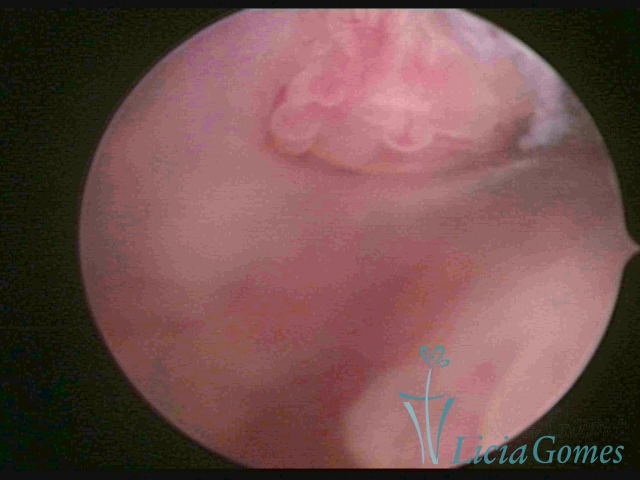

ENDOCERVICAL POLYPS

Benign tumors resulting from the reactive focal proliferation to inflammatory processes or hyperestrogenism situations, which may be sessile (with a large implantation) or stalked.